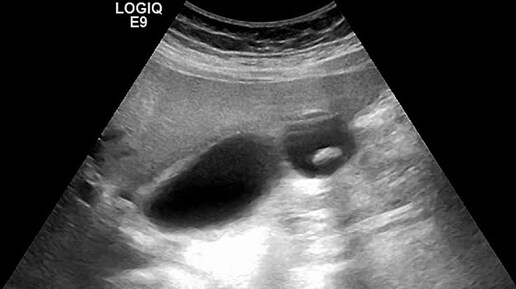

Ультразвуковые находки от врача УЗД Зорина Я.П.

Видео к статье "Ох уж эти перегибы..."https://dzen.ru/a/Z_-nbMj2F2BXtnMj